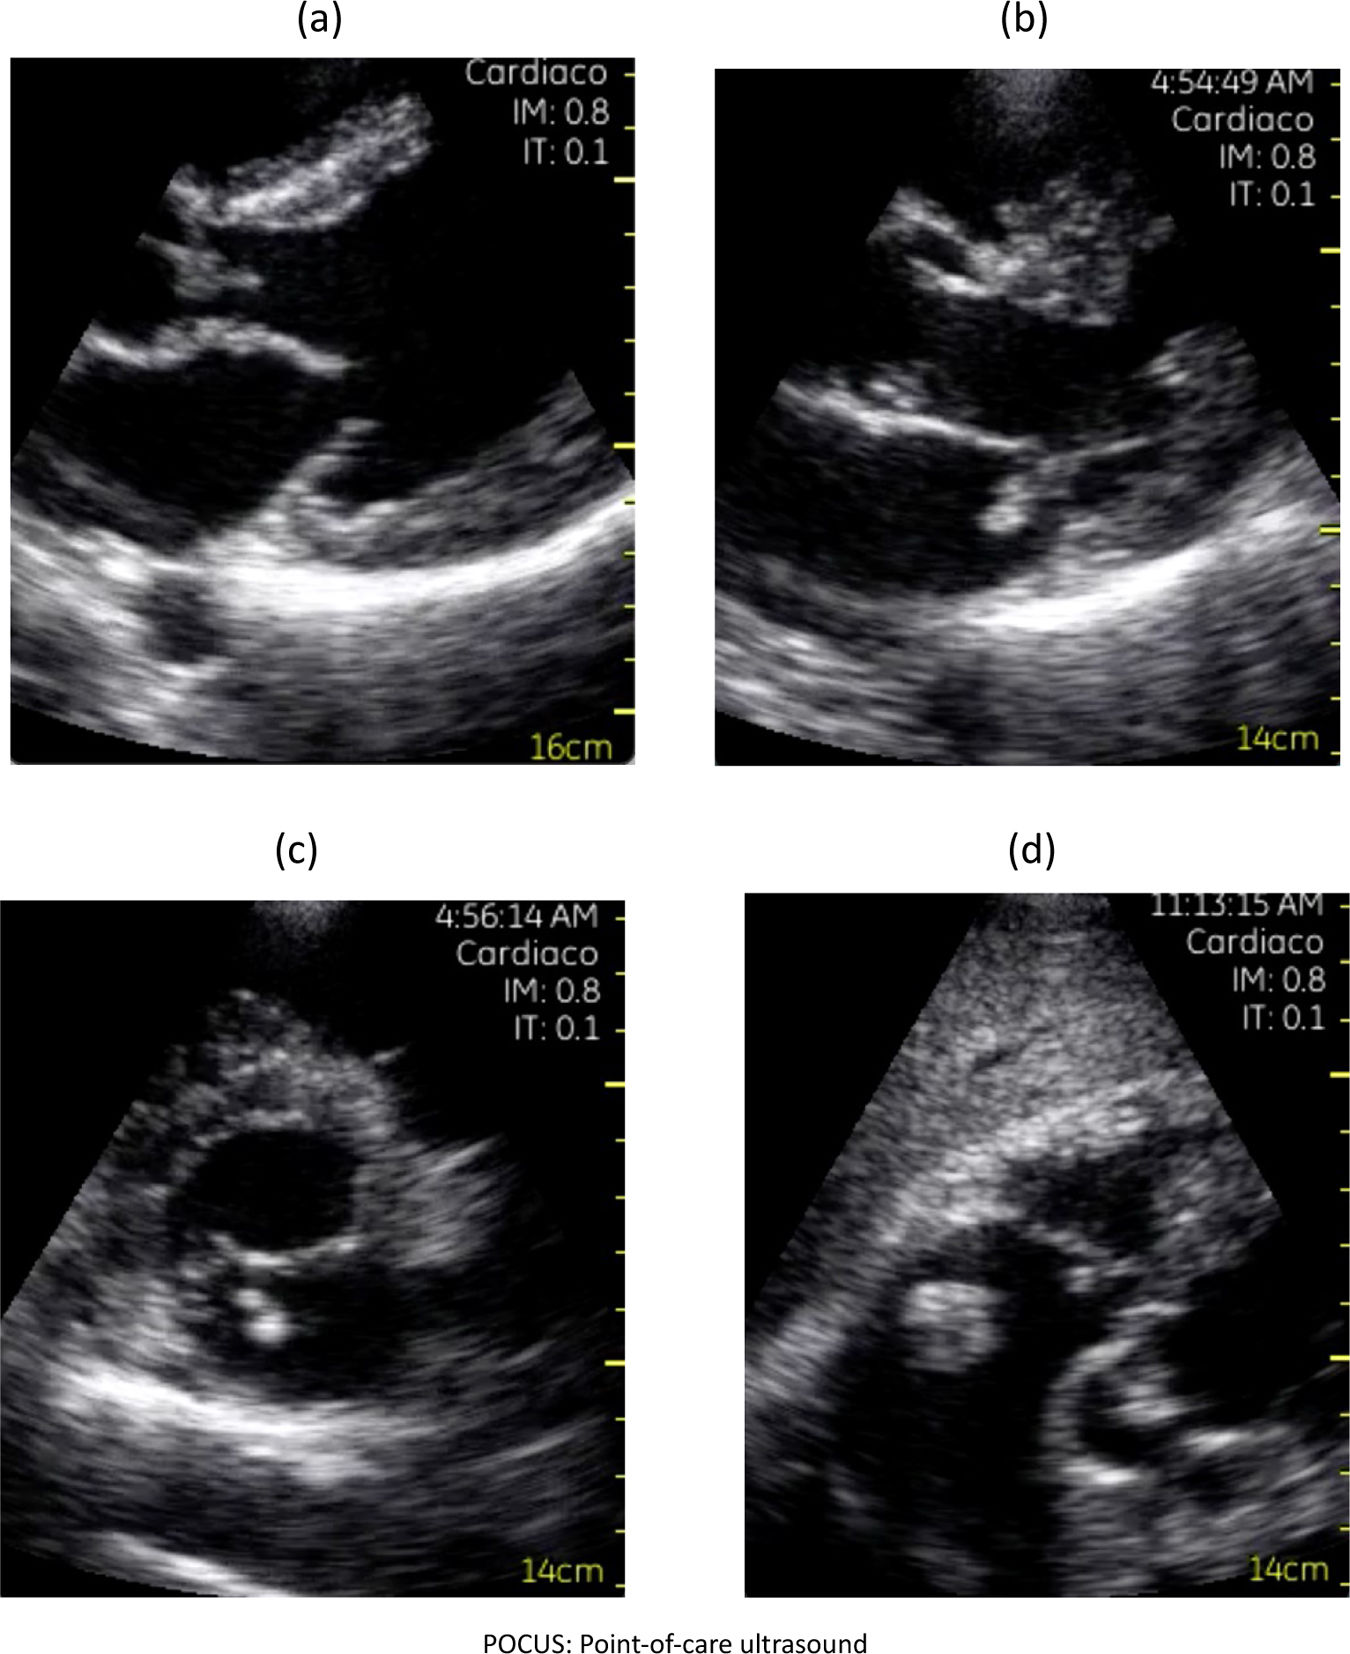

A narrative review assessed the utility of point-of-care ultrasound (POCUS) in evaluating suspected infective endocarditis (IE). MEDLINE, EMBASE, and Google Scholar were searched for studies published from January 1, 2010 to January 31, 2025. Data extraction was performed independently by three authors. Thirty-five studies involving 293 participants were included, the majority being case reports. For detecting valvular vegetations, POCUS demonstrated a sensitivity of 77% and a specificity of 94%. POCUS may serve as a useful adjunct to bedside physical examination, facilitating the detection of echocardiographic findings suggestive of IE and other endovascular infections. Nonetheless, the predominance of case reports, which represent the lowest level of clinical evidence, substantially limits the external validity and generalizability of these results. Further high-quality studies are warranted to confirm the diagnostic performance and clinical impact of POCUS in this setting. Overall, POCUS shows promise but evidence remains limited by study design.

Se realizó una revisión narrativa sobre la utilidad del ultrasonido en el punto de atención (point-of-care ultrasound [POCUS]) en pacientes con sospecha clínica de endocarditis infecciosa (EI). Se buscaron estudios publicados entre el 1 de enero de 2010 y el 31 de enero de 2025 en MEDLINE, EMBASE y Google Scholar. Tres autores extrajeron los datos de forma independiente. Se incluyeron 35 estudios con 293 participantes, la mayoría reportes de casos. POCUS mostró una sensibilidad del 77% y una especificidad del 94% para detectar vegetaciones valvulares. Como herramienta complementaria a la exploración física a pie de cama, POCUS puede facilitar la identificación de hallazgos ecocardiográficos sugestivos de EI y otras infecciones endovasculares. Sin embargo, el predominio de reportes de casos, que representan el nivel más bajo de evidencia clínica, limita considerablemente la validez externa y la generalización de los resultados. Se requieren estudios de mayor calidad para confirmar estos hallazgos.